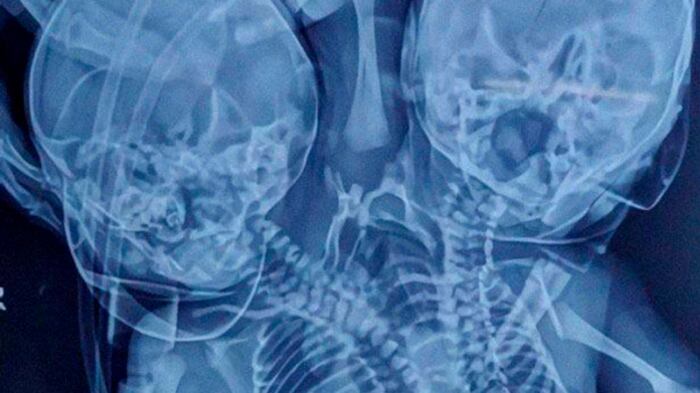

Los médicos le habían indicado que iba a dar a luz a unos mellizos, sin embargo, el día del parto la historia fue otra. El 28 de marzo de 2022 nació un bebé con dos cabezas, tres brazos y dos corazones en la India.

Uno de los médicos que atendió el parto explicó que esta condición de nacimiento se conoce como parapagus dicefálico. Esto significa que cuando dos bebés están unidos por un solo torso. Agregó que comúnmente estos embarazos terminan con la muerte de los fetos.